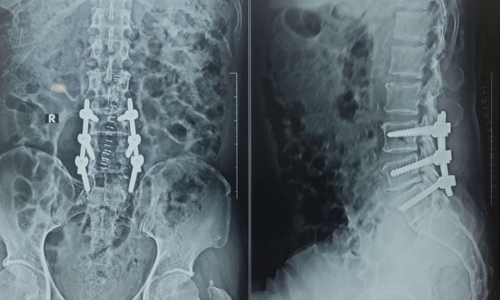

Cervical Myelopathy

Cervical Myelopathy Expert Care by Dr. Nitish Agrawal – Best Spine Surgeon in Pune Cervical Myelopathy is a serious spinal condition in which the spinal cord in the neck (cervical spine) becomes compressed. This compression is most commonly caused by degenerative changes in the spine, such as cervical disc prolapse,…